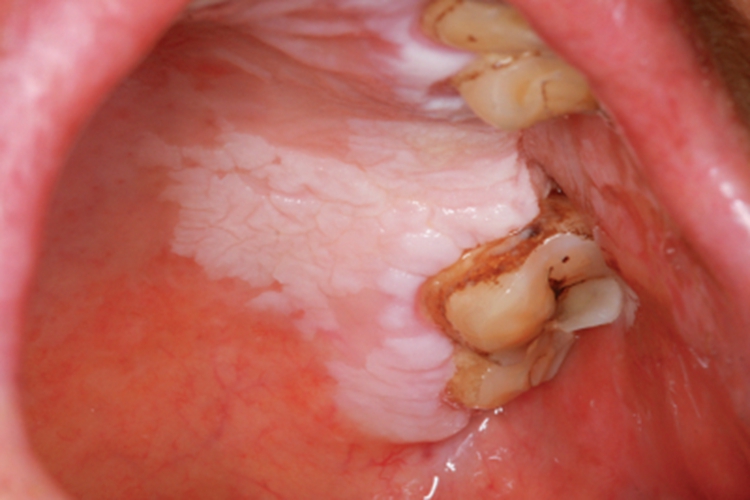

口腔白斑病患者口腔的损害形态多样,包括斑块状、溃疡状等,颜色分布不均,边界清楚,形状不规则,表面凹凸不平,患处质地柔软,患者一般无自觉症状,或自觉粗糙、木涩等。